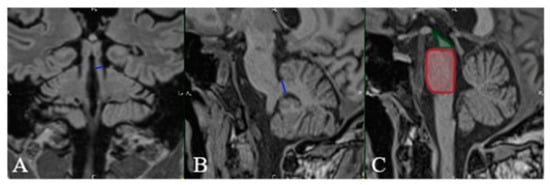

| Positive “hummingbird” sign. |

| Positive “Mickey mouse” sign. | ||||

| Positive “horning glory” sign. | ||||